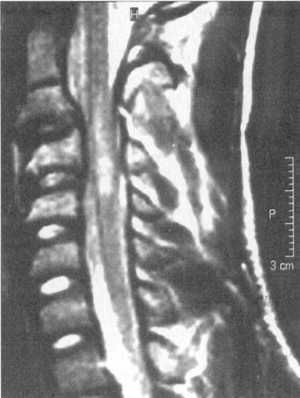

Ценную информацию о состоянии вывихнутых позвонков и спинного мозга дает

МРТ (рис. 2.6, 2.7). МРТ позволяет определить наличие зон ишемии в спинном

мозге (рис. 2.8, 2.9), состояние ликвородинамики (рис. 2.10).

Рис. 2.8. Компрессионный перелом с подвывихом кзади С4 позвонка

с зоной ишемии спинного мозга

Рис. 2.9. Вывих С4-С5, позвонков с зоной ишемии спинного мозга